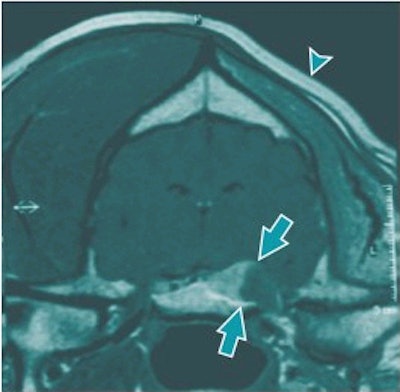

![]() |

| An MRI of an 8-year-old golden retriever dog. Buzzie presented with weight loss and severe left-sided facial muscle atrophy (arrowhead). The MR exam revealed a partially contrast-enhanced tumor of the trigeminal nerve (CNV, arrows) that is evident within the cranial vault and exits through the foramen at the level of the temporomandibular joints. Image courtesy of Animal Imaging of Los Angeles. |